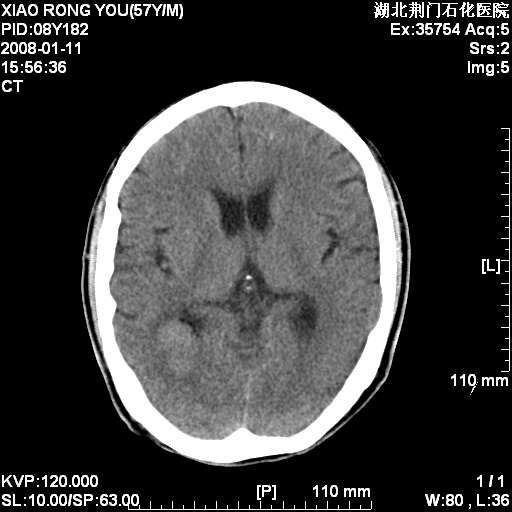

1月后复查

转移瘤,前后对比可发现复查片左顶叶出现一低密度灶

病变范围在一个多月时间增大,且密度不均周围有税种,并且多发!考虑转移瘤!

左枕/顶叶出现新病灶,转移瘤